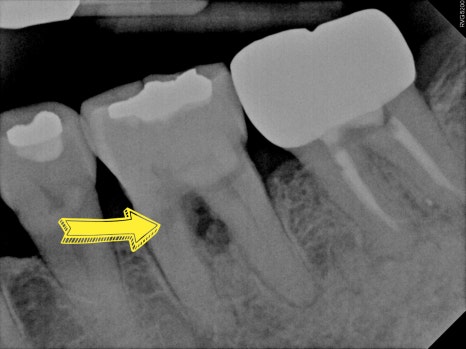

CASE 1. " 잇몸이 욱씬하고 고름이 나와요"

치주염으로 인해

치아 뿌리가 갈라지는 부위의 잇몸뼈가 소실되어

치아 지지력이 약해져 있던 케이스 입니다

염증 조직을 제거한 뒤

엠도게인 치주 재생 치료를 진행하였고,

치료 후 약 2개월 경과 관찰 시

치아 사이 잇몸뼈가

점차 회복되는 양상을 확인할 수 있었습니다